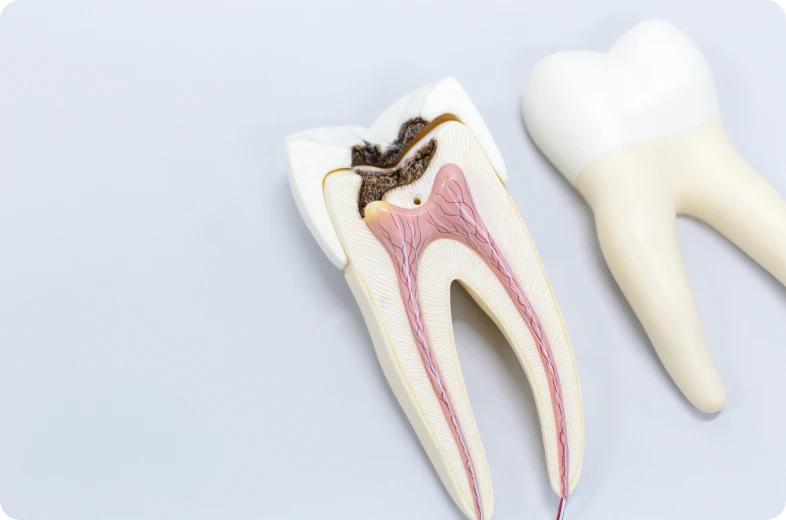

Les résorptions dentaires correspondent à un processus biologique entraînant la destruction progressive des tissus durs de la dent. Ce phénomène touche principalement la dentine, mais peut également concerner le cément et, plus rarement, l’émail. Il résulte de l’activité de cellules appelées odontoclastes, dont le rôle est de résorber les tissus minéralisés.

Les résorptions internes prennent naissance à l’intérieur de la dent, au niveau de la pulpe. Elles sont généralement associées à une inflammation pulpaire chronique, parfois liée à un traumatisme ancien, une carie profonde ou une irritation prolongée.

La destruction progresse vers les parois du canal radiculaire. L’aspect extérieur de la dent reste souvent inchangé, ce qui rend le diagnostic difficile sans imagerie. Dans certains cas, une modification de la teinte peut apparaître.

Sans prise en charge, la résorption interne fragilise la structure dentaire. Une détection précoce est essentielle.